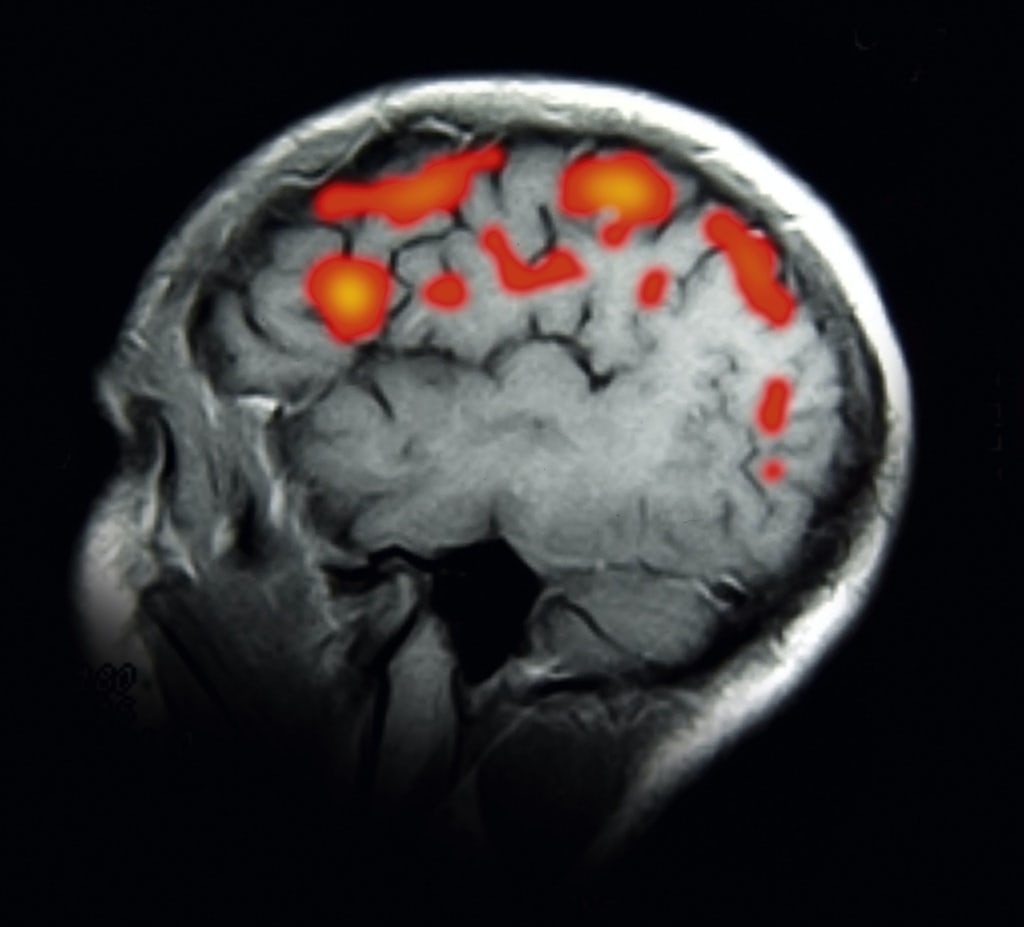

Psykiske sykdommer kan ses i hjernen

-Tidligere trodde man at psykiske lidelser kom av ubalanse i sinnet, og ikke hadde fysiske årsaker. Men nå kan forskerne avlese sykdommene i hjernen. Dels er det hjernesentre som enten er større eller mindre enn hos friske personer, og dels er det forstyrrelser i forbindelsene i hjernen.

Benbrudd, sukkersyke, kreft og mange andre sykdommer er håndfaste for legene fordi de er knyttet til skadet vev, unormale måleresultater eller infeksjoner som er til å få øye på. Det gir et godt utgangspunkt for å forstå sykdommens årsak og finne en behandling, og legene kan følge sykdomsforløpet slik at de hele tiden kan vurdere om pasienten er i bedring eller helt kurert.

Men inntil for få år siden har en stor gruppe sykdommer vært aktive i det skjulte. Legene har kunnet se symptomene, men ikke årsakene. Det dreier seg om psykiske sykdommer – for eksempel depresjon og schizofreni – som riktignok har sitt utspring i hjernen, men ikke setter tydelige spor i form av ødelagte nerveceller eller unormale analyseresultater.

I mange år har man trodd at disse symptomene bare hadde psykiske årsaker og måtte bygge på vrangforestillinger, noe man i beste fall kunne kurere gjennom samtale der pasienten ble ledet frem til å forstå sin egen situasjon og deretter hjelpe seg selv ut av den. Selv om kognitiv terapi og andre former for psykologisk bistand er gode verktøy til behandling av psykiske lidelser, har man etter hvert innsett at de ikke kan stå alene.

Nervesignalene følger andre spor:

Mange sykdommer i sinnet har håndfaste, fysiske årsaker, og derfor kan de i likhet med et brukket ben ikke bare snakkes bort. Hjerneskanning og andre nye teknikker har avslørt at selv om hjernen hos psykisk syke pasienter kan se normal ut, følger nervesignalene ofte andre ruter enn i hjernen hos en frisk person.

Hjernen er slik innrettet at ulike områder håndterer hver sin høyt spesialiserte funksjon som ikke kan løse en praktisk oppgave alene. Vår umiddelbare reaksjon på for eksempel en fornærmelse er styrt av et nært samspill mellom sentrene for blant annet situasjonsanalyse, hukommelse, vrede, selvkontroll og beslutningstaging, og hvis bare ett av disse leddene svikter, risikerer vi å reagere urimelig aggressivt eller helt apatisk.

Selv om forskerne fortsatt mangler den store oversikten, vet de nå at mange sinnslidelser skyldes at noen av de spesialiserte sentrene ikke fungerer korrekt, eller at de ikke kommuniserer på riktig måte med hverandre.

Ofte er det en genetisk forklaring på slike feil, slik at man fra fødselen av kan ha økt risiko for å utvikle eksempelvis depresjon, schizofreni eller posttraumatisk stressyndrom. Det betyr ikke at man automatisk blir rammet av disse sykdommene, men at hjernen er dårligere rustet til å takle stress eller traumatiske opplevelser, og at de derfor kan bringe de nevrale nettverkene inn på et feilaktig spor og få psykiske sykdommer til å bryte ut.

Forskernes gryende forståelse for årsakene til sykdommer i sinnet har åpnet nye behandlingsmuligheter, blant annet en moderne versjon av elektrosjokk, Deep Brain Stimulation.

I tillegg har legene fått bedre mulighet til å utpeke personer som befinner seg i særlige risikogrupper. Det kan for eksempel føre til at soldater med økt risiko for å utvikle posttraumatisk stressyndrom ikke blir sendt på farlige oppdrag, der det er stor fare for at traumatiske opplevelser kan utløse sinnslidelsen.